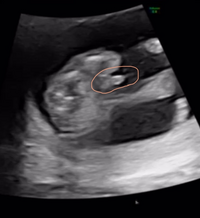

妊娠15週目の妊婦です 先日のエコーで男の子の突起物みたいなも Yahoo 知恵袋

医師監修 妊娠15週のエコー写真を多数掲載 みんなのエピソードつき Michill ミチル

妊娠15週目 15w0d 6d のエコー写真とエピソード 妊娠4ヶ月 Cozre コズレ 子育てマガジン

妊娠15週目エコー写真や胎児の大きさ 胎動 お腹の張りは 妊娠初期 All About